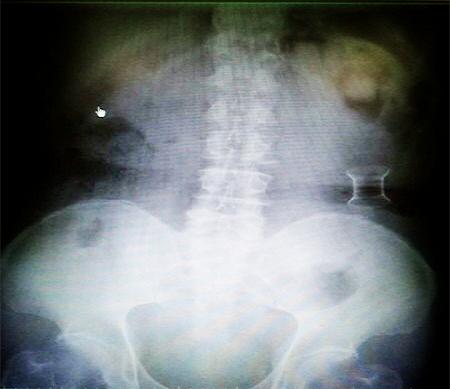

受試患者在結(jié)腸端端吻合術(shù)中,使用我司新研制產(chǎn)品達(dá)到了理想的預(yù)期效果。患者術(shù)后7天、14天X光片顯影,可降解腸道支架均能按研制設(shè)計(jì)的預(yù)期時(shí)間節(jié)點(diǎn)保持應(yīng)有強(qiáng)度,術(shù)后21天X光片顯示可降解腸道支架已完全破碎,并排出體外。在整個(gè)試驗(yàn)過程中,病患無任何不良反映,耐受良好。